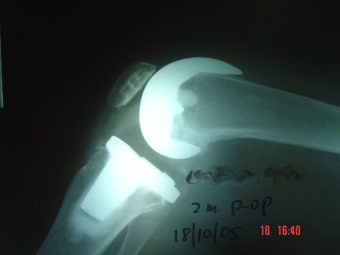

Artrosis de rodilla derecha por valgo severo

Envíado por Dr. Ricardo Antonio Gómez G.